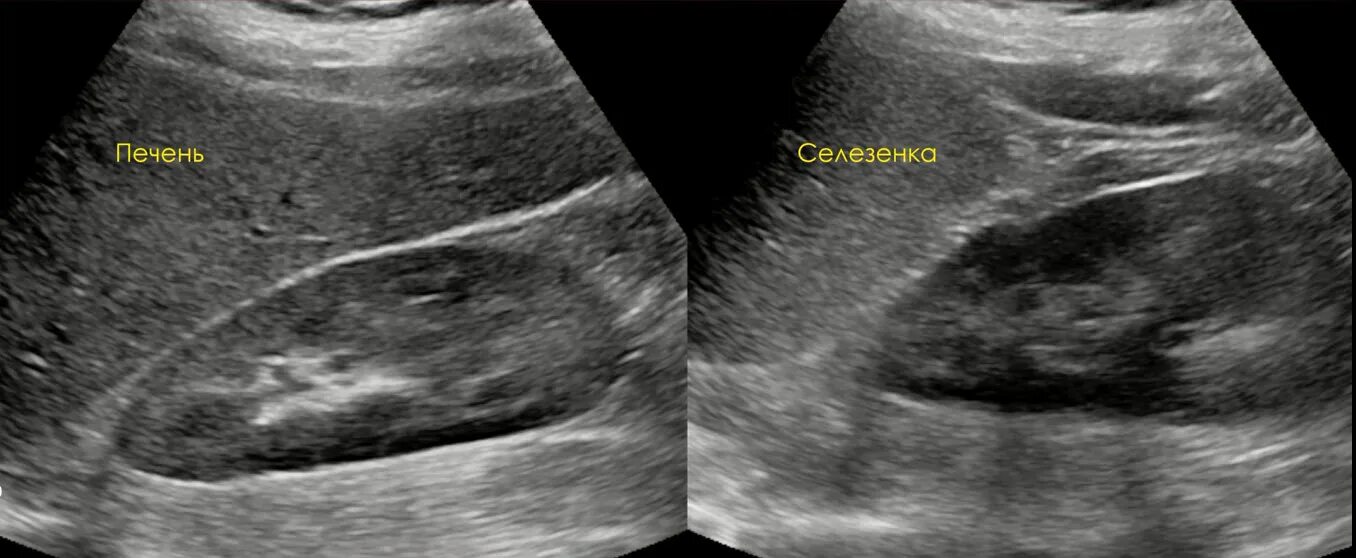

Гиперэхогенные структуры на узи. мелкие гиперэхогенные структуры в почках на узи. гиперэхогенная структура паренхимы печени. гиперэхогенные включения в печени на узи.Гиперэхогенные образования в печени на узи.Доброкачественные опухоли печени на узи. гиперэхогенные образования в печени на узи. гиперэхогенные включения в печени на узи.Узи селезенки гиперэхогенные образования. гиперэхогенное образование в печени. гиперэхогенные образования в печени на узи. гиперэхогенные структуры на узи.Гиперэхогенные включения в печени на узи. узи селезенки гиперэхогенные образования. гиперэхогенное образование в селезенке.Гиперэхогенное включение в печениГиперэхогенное образование в печени на узи что это такое. газ в портальной системе печени на узи. гиперэхогенные включения в печени на узи. гиперэхогенные точечные включения в селезенке на узи.Гиперэхогенная печень. гиперэхогенные образования в печени. гиперэхогенная печень на узи. гиперэхогенное образование в печени на узи что это такое.Гиперэхогенные включения в печени на узи. холангит на узи.Узи анатомия почек. гиперэхогенные линейные структуры. точечные гиперэхогенные включения в печени. гиперэхогенные включения в миометрии.Гиперэхогенное включение в печениТочечные гиперэхогенные включения в печени. гиперэхогенное образование в почке что это. симптом гиперэхогенных пирамид в почках на узи. гиперэхогенные тяжи на узи.Гиперэхогенные структуры на узи. гиперэхогенные включения без акустической тени. узи селезенки гиперэхогенные образования. гиперэхогенное образование в печени на узи что это такое.Гиперэхогенные включения в печени на узи. амебный абсцесс печени на узи. гиперэхогенный очаг в печени. неоднородное образование в печени на узи.Метастатическое поражение печени узи. образования печени на узи. гиперэхогенные образования.Гиперэхогенное включение в печениГиперэхогенные образования. гиперэхогенное образование на узи. гиперэхогенные образования в печени.Метастазы в печень гиперэхогенные узи. гиперэхогенное образование. гиперэхогенные включения. множественные гиперэхогенные включения в печени.Гиперэхогенные включения поджелудочной железы. гиперэхогенные включения в печени на узи. узи множественные гиперэхогенные. кальцинаты в простате на узи.Подкапсульная гематома печени на узи. гиперэхогенные образования в печени. гиперэхогенные включения в печени. гиперэхогенное образование в печени по узи.Гиперэхогенные образования в печени на узи. гепатоцеллюлярная аденома печени узи. гиперэхогенный очаг в печени на узи. очаговый липоматоз печени узи.Гиперэхогенные образования. множественные гиперэхогенные образования. гиперэхогенные образования в печени. образование брюшной полости узи.Гиперэхогенное включение в печениГиперэхогенная печень. гиперэхогенный желчный пузырь. гиперэхогенное образование в желчном пузыре. гиперэхогенные образования в печени.Узи желчного пузыря гиперэхогенные. гиперэхогенный желчный пузырь узи. гипоэхогенное образование в желчном пузыре. гиперэхогенное образование в желчном пузыре.Гиперэхогенное включение в печениГиперэхогенный полип эндометрия. гиперэхогенное. множественные гиперэхогенные образования.Гиперэхогенное включение в печениГиперэхогенные образования в печени на узи. гипоэхогенные образования в печени метастазы. гипоэхогенное образование при узи печени.Гиперэхогенное включение в печениГиперэхогенное неоднородное образование в печени. гиперэхогенные структуры. в полости матки гиперэхогенное образование. гиперэхогенные линейные структуры.Гиперэхогенные включения в печени на узи. гиперэхогенный очаг в мочевом пузыре.Гиперэхогенные участки на узи. гиперэхогенное включение. гиперэхогенные включения в яичнике.Гиперэхогенное включение в печениКонкремент в мочевом пузыре узи протокол. линейное гиперэхогенное образование. гиперэхогенное образование на узи.Синдром гиперэхогенных пирамид почек узи. узи селезенки гиперэхогенные образования. гиперэхогенные включения в печени на узи. образование почки на узи в паренхиме.Гиперэхогенное образование на узи. узи анатомия почек. точечные гиперэхогенные включения в печени.Сонограмма поджелудочной железы. кольцевидная поджелудочная железа узи. гиперэхогенное образование поджелудочной железы узи. гиперэхогенные включения в печени на узи.Гиперэхогенная структура на узи. гиперэхогенное образование на узи. гиперэхогенное образование диаметром 21 мм. гиперэхогенные включения до 3-4 мм.Гиперэхогенные включения. гиперэхогенные включения в матке. гиперэхогенное точечное включение. гиперэхогенные включения в цервикальном канале.